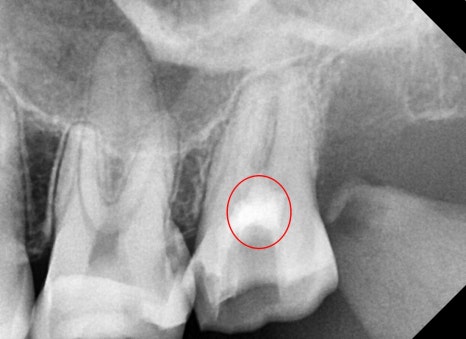

사진에 표시된 화살표처럼

치아를 가로지르는 선명한 크랙 즉, 금 간 것이 보이실 겁니다.

이상하게도 그때도 증상이 거의 없으셨고,

환자분께서 발치는 거부감이 있으셔서

마지막 시도로 MTA를 사용한 케이스였는데

얼마 전에 치료 후 1년 되는 시기에 내원을 해주셨습니다.

특별하게 엑스레이, 육안상, 검사상에서도

특별한 문제는 발견되지 않았습니다.

예후가 많이 좋지 않았지만 1년째까지 너무 다행이지만

한편으로는 자주 내원하게 해드려서

교합이나 증상 체크를 잘해드려야겠다는 생각도 들었습니다.

지금도 이 정도로 금이 가서 오신 환자분이 계시다면

저는 발치를 권해드릴 것 같습니다.

MTA가 만능이 아니라 여러 상황이 재료의 장점을 극대화해줬던 것 같습니다.